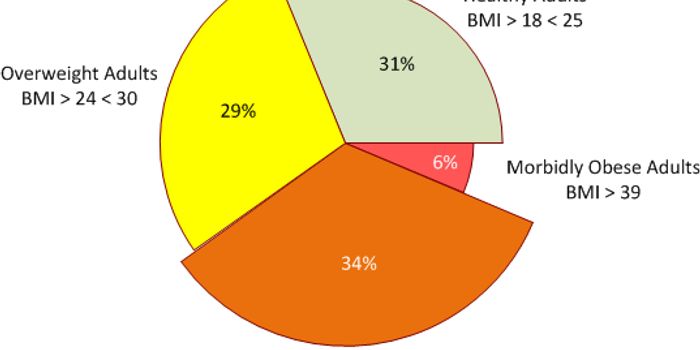

MAY 06, 2024CancerObesity, a chronic disease characterized by an unhealthy amount of body fat, confers a high risk of several types of can ...

AUG 29, 2017CancerIt’s no secret that obesity is a risk factor for several health conditions, including cancer. But specific to canc ...